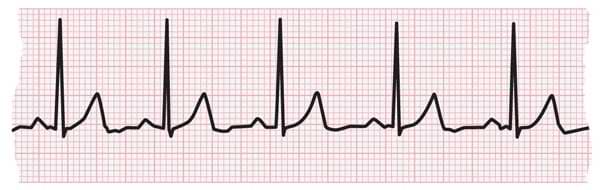

Atrial flutter is a kind of abnormal heart rhythm (arrhythmia). Atrial flutter happens when the upper chambers beat faster than normal and are coordinated. It is not as common as atrial fibrillation, also known as AFib or AF. But atrial flutter has similar symptoms, causes and results. People with atrial flutter may also develop AFib. An electrocardiogram can detect atrial flutter.

During atrial flutter, the upper chambers of the heart, also called the atria, beat 250 to 350 times per minute. With atrial flutter, the signal that tells the atrium to beat may be blocked by damaged tissue or scar tissue.